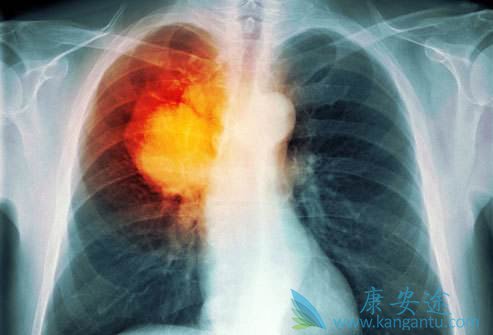

肺癌晚期治疗方案选择要参考患者情况

由于肺癌的生长部位、TNM分期、病理分型、基因分型、副癌综合征较为复杂,加之患者的年龄、体力状况评分(PS评分)、合并症等个体差异,其临床表现、治疗原则各不相同。特别是肺癌晚期患者的治疗就更要慎重。

目前第三代化疗药物联合铂类的双药化疗方案,提高了肺癌晚期治疗的效果,提高了晚期非小细胞肺癌患者的总生存期,但其疗效已达平台,很难有突破性的进展。随着分子生物学、药物基因学及高通量测序技术的发展和普及,个体化治疗是必然趋势。

多数肺癌晚期的患者丧失手术机会,且部分患者在传统放化疗的治疗中获益较少,尤其一部分患者存在大气道狭窄或梗阻、气管食管瘘等情况,药物治疗很难缓解症状。

介入治疗操作相对简单、并发症少、重复性强、近期效果明显、患者易接受,可以明显改善患者的症状,应用前景看好。但是,由于介入治疗的远期效果不理想,它不能替代手术、放化疗和靶向治疗等基本治疗手段。